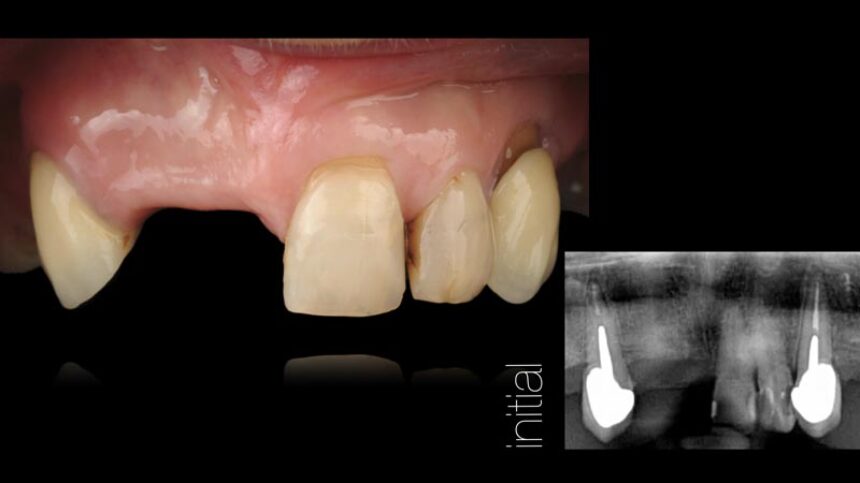

The congress will also feature Dr. Iñaki Gamborena whose lectures will focus on the key factors affecting the success of treatment in the aesthetic zone, both in patients with a purely dental arch and in implant restorations. His presentations will include the surgical and the prosthetic management of these cases, and he will also elaborate on the management of complex cases with past failures.

Aesthetic Implant Dentistry – basic science

Anatomical determinants of aesthetic implant restoration – Diagnosis and treatment planning.

Soft Tissue management.

Surgical techniques for hard and soft tissue augmentation.

Managing failures with implants in the esthetic area, the options.